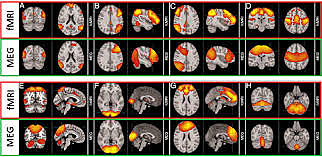

• Magnetoencefalografía

Magnetoencefalografía

Se realiza mediante neuromagnetómetros, calcula el origen de señales determinadas del encéfalo. Verifica la actividad cerebral.

• Tomografía computarizada (TAC) y Resonancia magnética

Tomografía computarizada (TAC) y Resonancia magnética

Buscan localizar la lesión en el encéfalo humano vivo,

La tomografía muestra secciones del encéfalo usando rayos X, mientras que la resonancia muestra secciones del encéfalo utilizando un campo magnético y ondas de radio.

• Tomografía por emisión de positrones TEP

Tomografía por emisión de positrones TEP

Técnica de neuroimagen no invasiva que brinda imágenes de la actividad cerebral